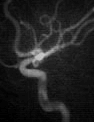

The first row shows results for an X-ray image of bones. The result of our model is compared to the result of M1) with the parameters proposed in the paper [26], i.e., and . The white part corresponds to positive values of the resulting function of the level set method M1). Furthermore, we depict the result of the two-step method M3) to show that correcting the illumination only in the preprocessing step before the segmentation is not sufficient. The methods M1) and M3) perform equally well, where each one shows different slight artifacts. The proposed model gives the best segmentation result, in particular the left bone and the upper part of the right bone are segmented correctly.

The second and third row show results for two CT angiography images of vessels. It is clearly necessary to incorporate the illumination since parts of the images differ widely in their brightness. For the first vessel image the parameters proposed in [26] were used. For the second vessel we set . The first segmented vessel by our method shows slightly thicker structures. In the image center the segmentation method M1) therefore gives better results. In the lower part M1) leads to too thin structure. Here our method performs better. M3) leads to the worst results in this example. Many thin structures are not corrected and some additional artifacts are visible. For the second vessel all three methods give good results. However, M1) and M3) show some small artifacts that are not visible with the proposed method.